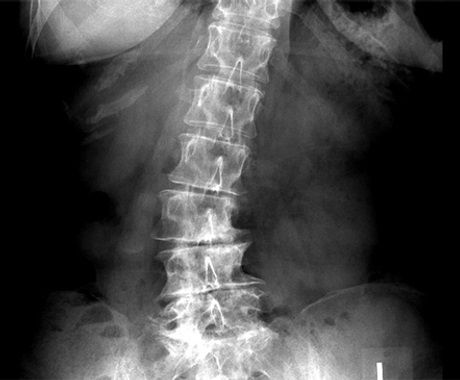

| Σκολίωση

Η Χειροθεραπεία είναι μια αποτελεσματική θεραπευτική προσέγγιση για την αντιμετώπιση του πόνου σε ενήλικες με σκολίωση.

Η Ιδιοπαθής σκολίωση θεωρείτε αγνώστου αιτιολογίας. Η Κρανιοϊερή Θεραπεία (Upledger) επιχειρεί να διαλευκαίνει το μυστήριο αποδίδοντας την αιτία μέσα στο Κρανιοϊερό και Περιτονιακό σύστημα του σώματος. Η προσαρμογή αυτών των συστημάτων σε πρότυπα τάσης, μπορεί να αποτελεί βασικό παράγοντα στη δημιουργία και την διατήρηση της σκολίωσης.